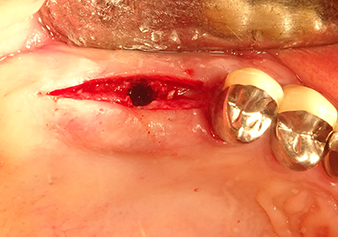

Une patiente de 49 ans, non fumeuse et sans antécédents médicaux remarquables, a été orientée vers notre cabinet de chirurgie orale pour l’extraction chirurgicale de la dent 16 préalable à la pose d’un implant. Après l’extraction, la patiente a rencontré de légers problèmes de sinusite, à la suite de quoi nous avons commencé par attendre six mois avant de prendre la mesure. À l’endroit prévu pour la pose de l’implant, l’os résiduel mesurait 3-4 mm de haut (Fig. 1 et 2).

Après la préparation atraumatique du lambeau muco-périosté, la position de l'implant est marquée à l'aide de l’insert I1 et le site préparé - jusqu’à la perception d’une résistance initiale. Les inserts de piézochirurgie sont utilisés suivant un mouvement ascendant et descendant, sans exercer aucune pression. La vibration piézoélectrique produit l’effet de cavitation souhaité, qui s’avère efficace.